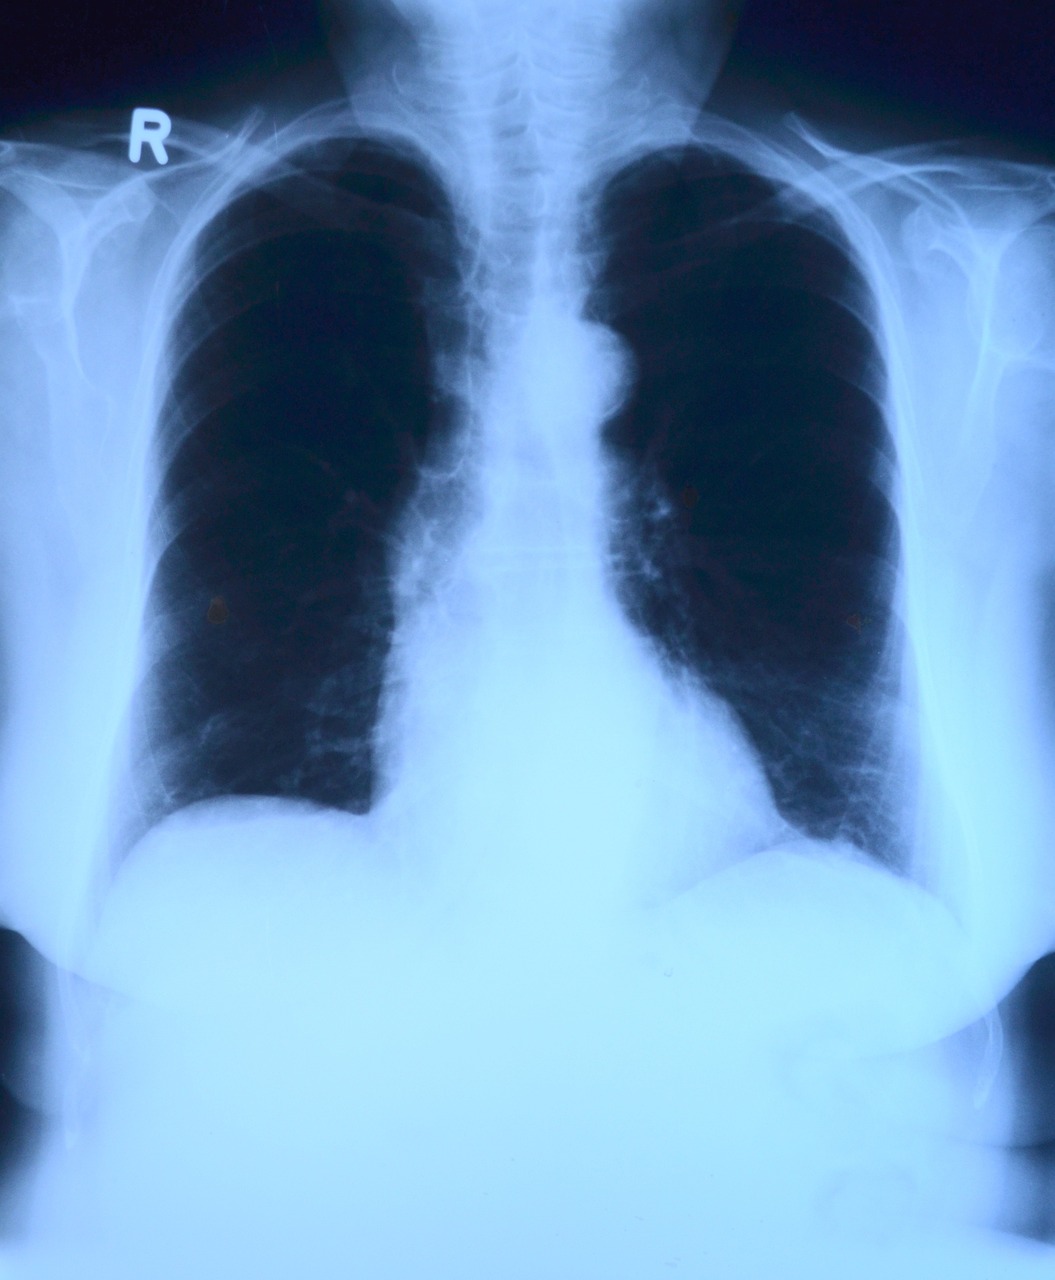

인체는 각각의 부분이 독특한 목적을 가지고 있는 복잡한 걸작입니다. 특히 호흡기는 산소와 이산화탄소의 교환을 촉진함으로써 생명을 유지하는 데 중요한 역할을 합니다. 이 복잡한 체계 안에는 폐를 덮고 흉막을 연결하는 이중 층의 막인 흉막이 있습니다. 그러나 염증이 흉막의 조화를 방해할 때 흉막염으로 알려진 상태에 이릅니다. 이 포괄적인 안내서에서 우리는 흉막염의 원인, 증상, 진단 및 치료 옵션을 탐구하면서 흉막염의 세계에 대해 자세히 설명할 것입니다.

의학적으로 흉막염이라고 불리는 늑막염은 흉막에 염증이 생기는 것이 특징입니다. 이 염증은 다양한 근본적인 요인들로부터 발생할 수 있습니다. 각각 개인들이 경험하는 짜증과 불편함에 기여합니다. 흉막의 몇 가지 일반적인 원인을 탐구해 봅시다: